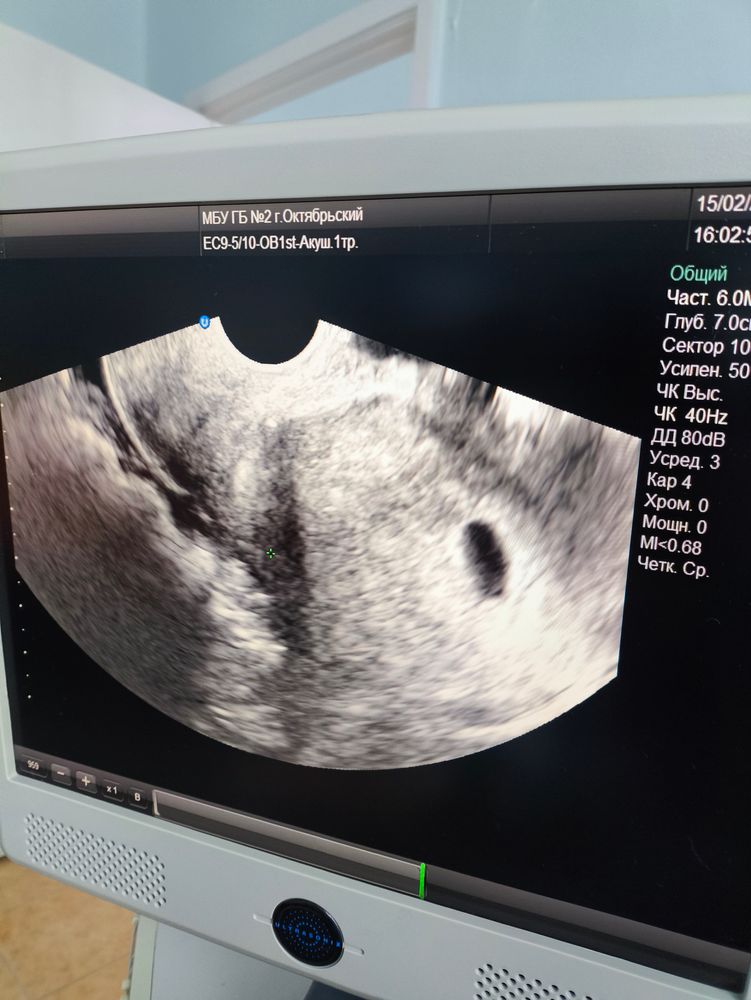

УЗИ 5н6д

Изображение

Девочки, ходила на прием в поликлинику. Врач повела на УЗИ . ПЯ есть, эмбриона не видно. Рано пошла? Или...

УЗИ в 5 недель

Последние М 01.12.24г. Т к тесты вовсю пестрят, пошла на УЗИ 🤩ПЯ 6 мм . Все хорошо🙏🤞 следующее УЗИ через пару неделек🤞